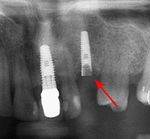

Bone loss (peri-implantitis) on implants over 7 years in a heavy smoker

Fixture show

Recession of the gingiva leads to exposure of the metal abutment under a dental crown.

Black triangles

Black triangles caused by bone loss between implants and natural teeth